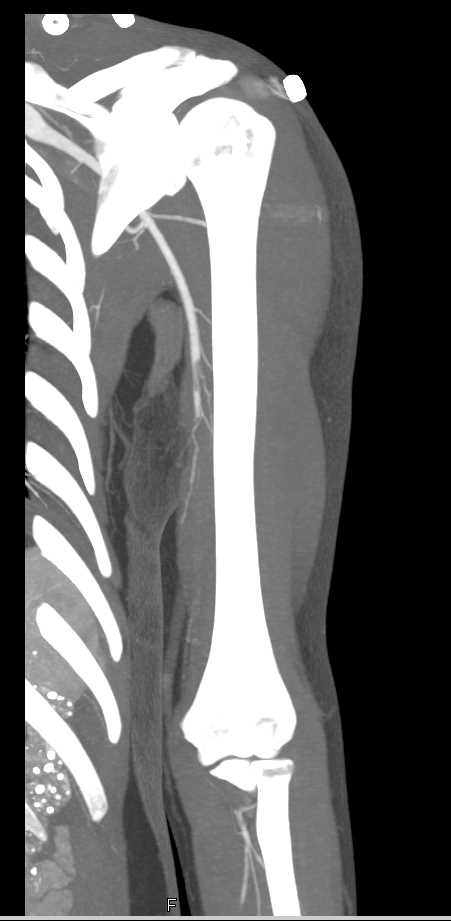

Brachial Artery Occlusion